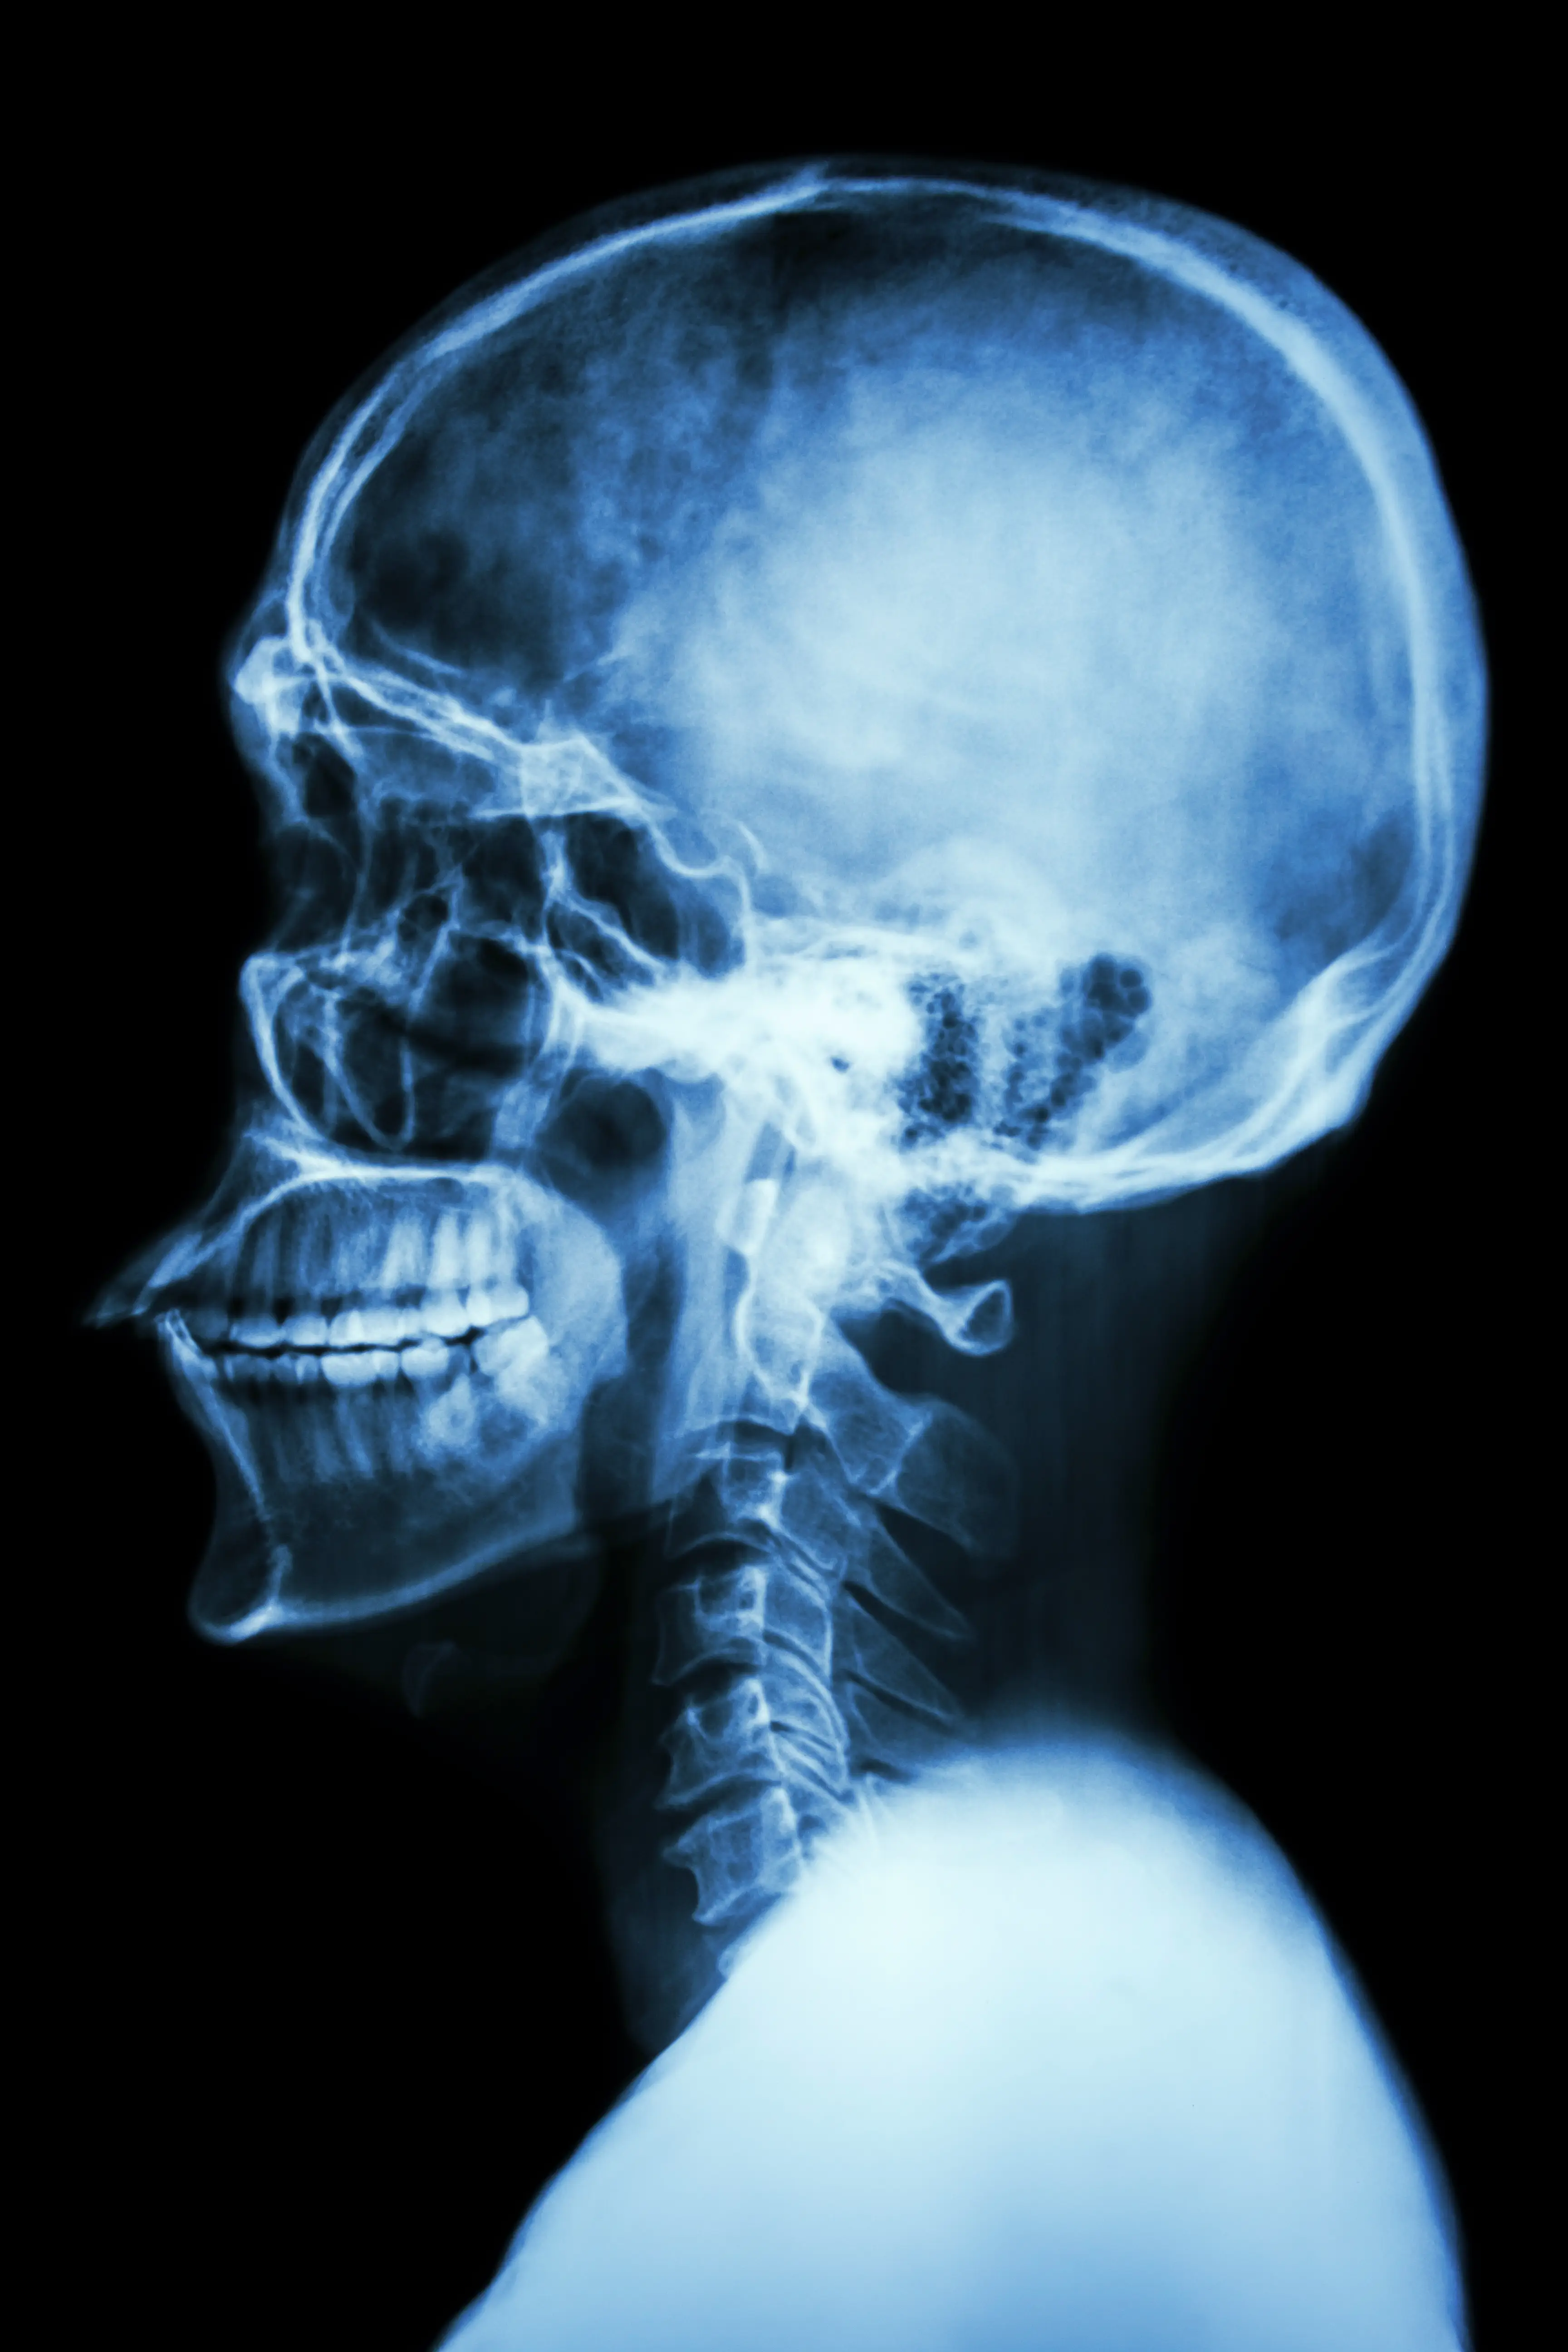

This is especially vital for cases of nasal injections, given that nasal blood vessels communicate with a number of important parts of the head and brain.